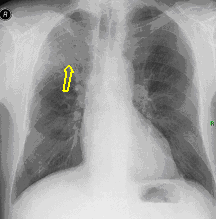

3a: Round shadow: multiple lung metastasis. Chest radiograph (PA)

3b: Multiple lung metastasis, CT lung window (axial, coronal reformat)

3c, coronal reformat

70 year old man, colon tumor.

Radiograph: Bilateral extensive, confluating patchy-nodular shadowing with diffuse reticular pattern. The diaphragm contour is partially blurry bilaterally: lymphangiosis carcinomatosa.

CT: Numerous 1-6 cm round and irregular, lobulated-spiculated contrast enhancing lesions in both lungs, everywhere sporadically.